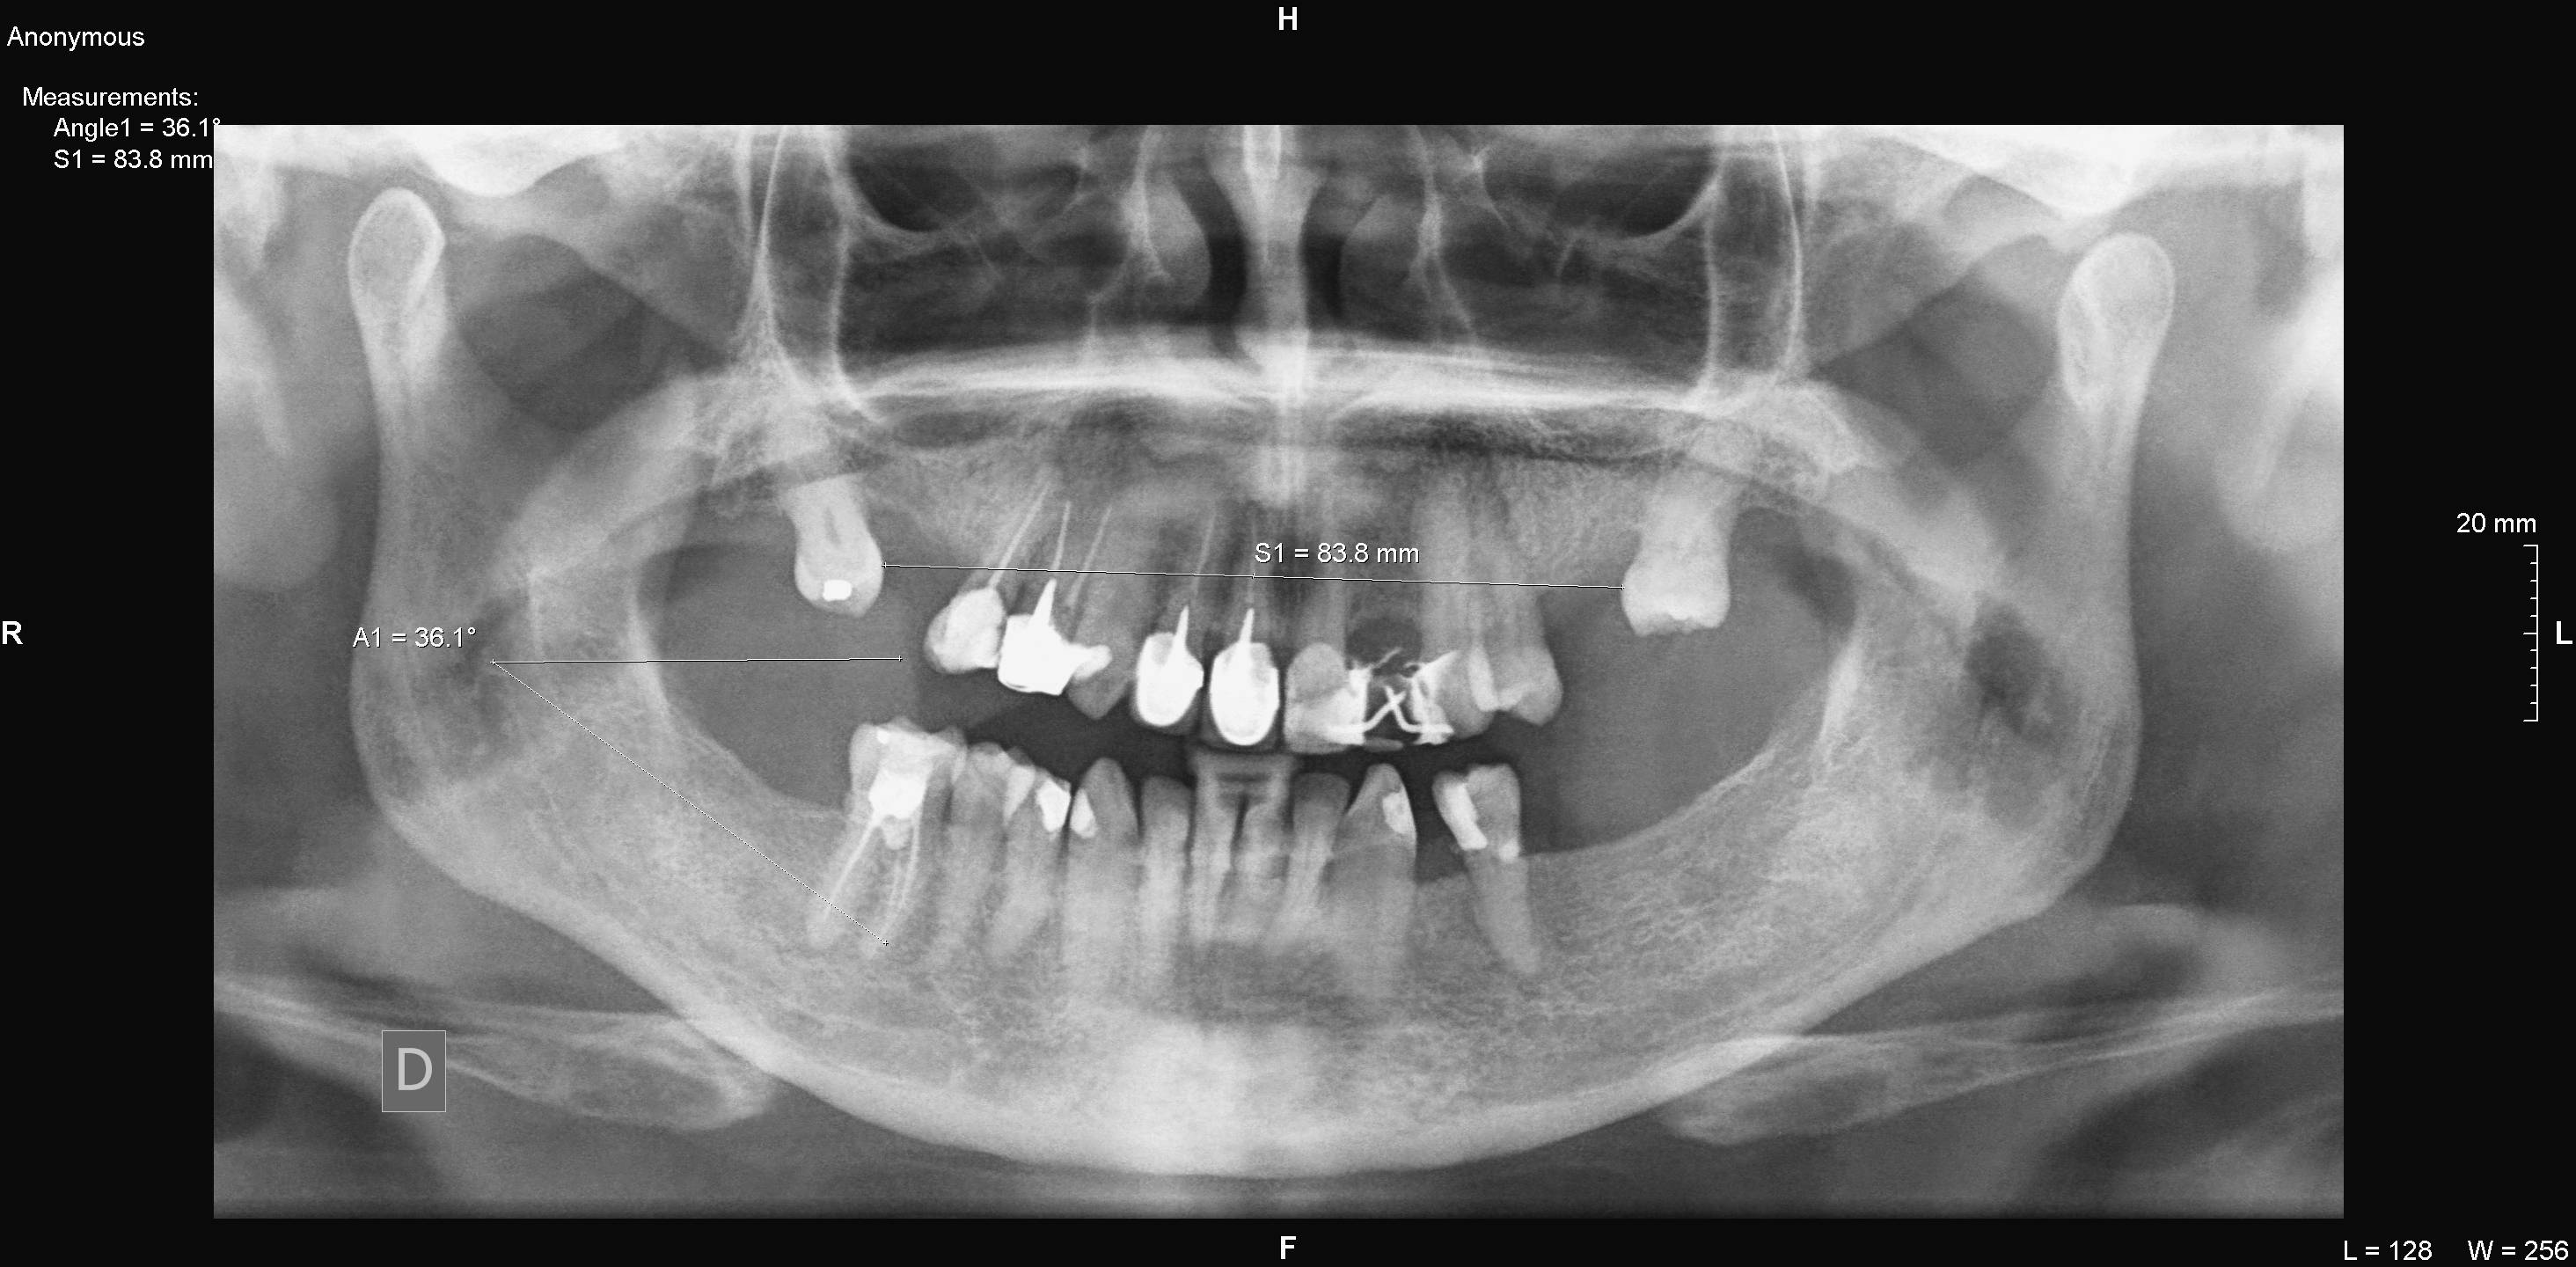

Algunos ejemplos de imágenes digitales

Pulse en las imágenes para ver la ampliación

Se agregó en rojo una medición hecha con la herramienta de medida